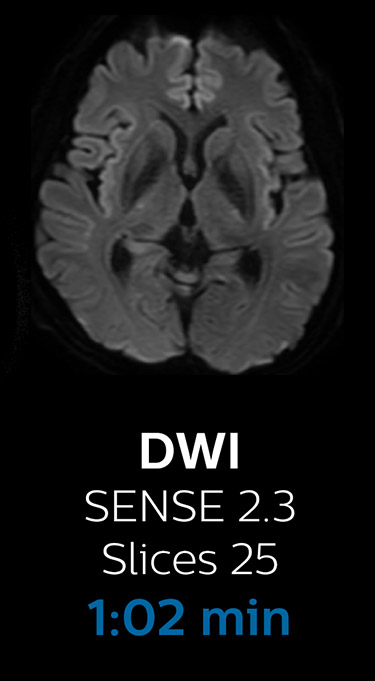

Scanning time reduction in brain MRI with Compressed SENSE

With Compressed SENSE, the scan time for the routine brain examination at KNC was reduced from 15:48 to 10:19 minutes, which corresponds to 35% reduction.

Brain with Compressed SENSE

Ingenia 3.0T CX

Scan time 10:19 min.